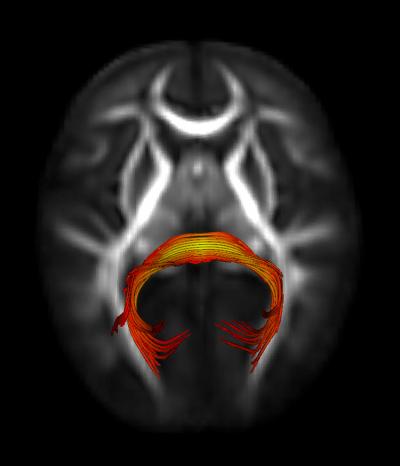

"These findings suggest that 7-month-olds who go on to develop autism show subtle, yet overt, behavioral differences prior to the emergence of the disorder. They also implicate a specific neural circuit, the splenium of the corpus callosum, which may not be functioning as it does in typically developing infants, who show more rapid orienting to visual stimuli," said Jed T. Elison, PhD, first author of the study.

The results showed that the high-risk infants later found to have ASD were slower to orient or shift their gaze (by approximately 50 miliseconds) than both high-risk-negative and low-risk infants. In addition, visual orienting ability in low-risk infants was uniquely associated with a specific neural circuit in the brain: the splenium of the corpus callosum. This association was not found in infants later classified with ASD.

The study concluded that atypical visual orienting is an early feature of later emerging ASD and is associated with a deficit in a specific neural circuit in the brain.